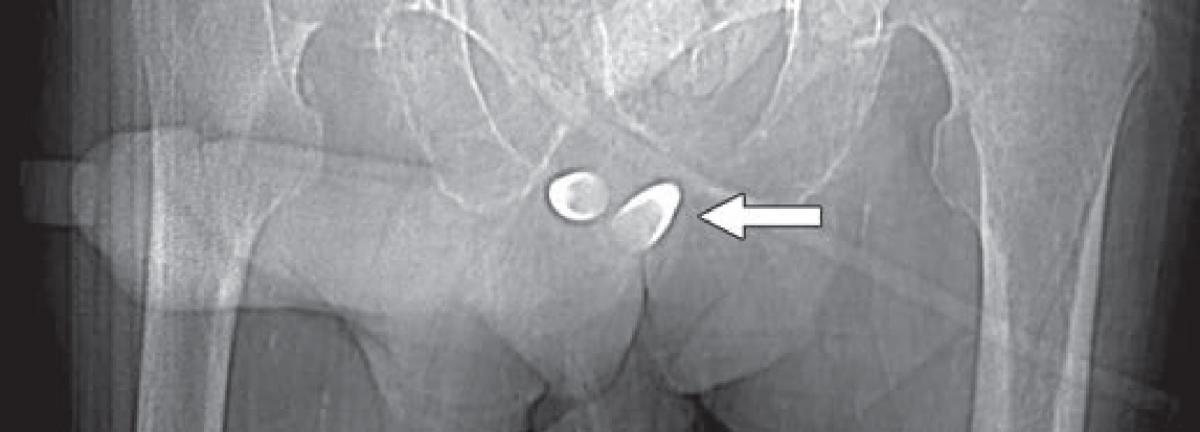

Scout image from contrast-enhanced CT shows erectile implant; stainless steel and silicone anchors (arrow) transfixed to pubic bone are asymmetric.

When evaluating urethral complications from phalloplasty in trans-males, because the neo-to-native urethra anastomosis site will evidence diameter differences, retrograde urethrograms can result in stricture overdiagnosis. Apropos, preliminary assessments should be for functional stricture, alongside the performance of urodynamic studies. “However,” noted Doo, “for confirmation of stricture with abnormal function tests and also for evaluation for fistula, a retrograde urethrogram or voiding cystourethrogram can be obtained.” Should a patient desire erectile potential with the fully-healed neophallus, an implant may be placed, which is prone to infection, attrition, malposition and constituent separation (Fig. 2).

Fig. 2 — Scout image from contrast-enhanced CT shows erectile implant; stainless steel and silicone anchors (arrow) transfixed to pubic bone are asymmetric.